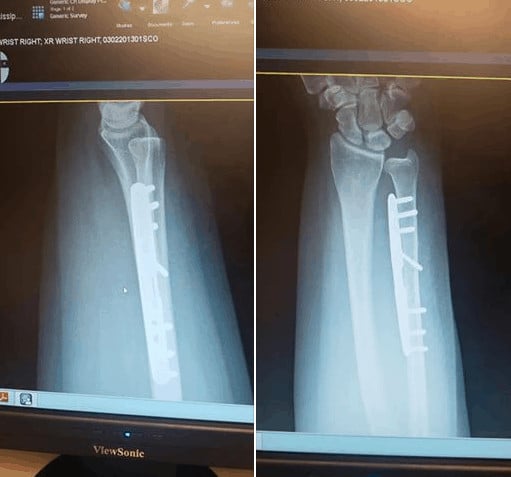

Above are photos of the plates and pins I now have in my bone.

After verifying the damage, he then made an incision in my arm, cut my bone diagonally and removed 4mm of length. It’s put back together with a plate and screws. The new space will prevent the bones from banging together and hopefully eliminate the pain and “popping” in my wrist.